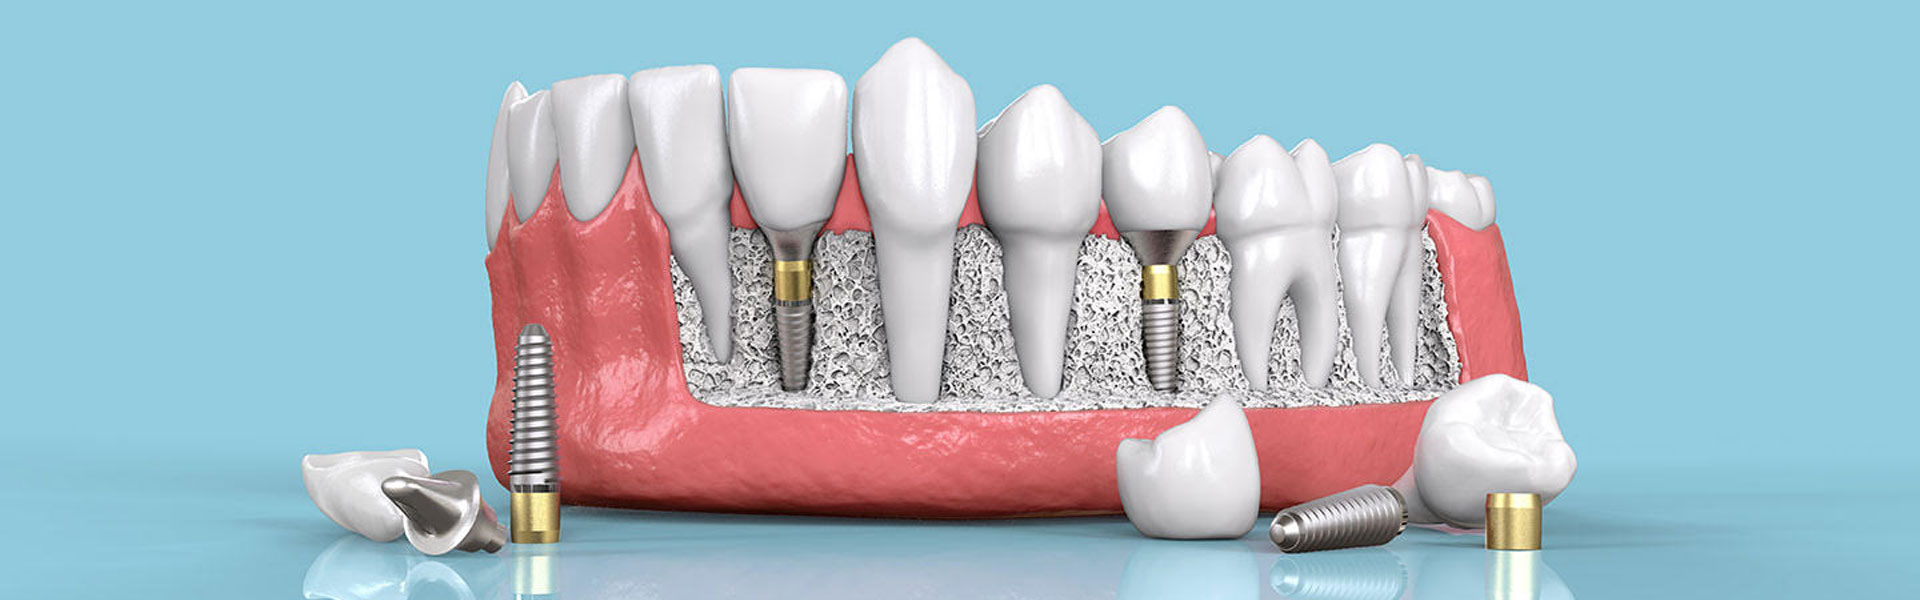

Suvremeno opremljena stomatološka ordinacija dr. Ante Lucin, djeluje na otoku Viru od 2003. godine i pruža sve vrste dentalnih usluga.

Vodeći se standardima suvremene stomatologije i najnovijih svjetskih trendova, svakom pacijentu pristupamo individualno i cjelovito.

Rješavanjem bilo kojeg dentalnog problema, garantiramo dugoročno zadovoljstvo svakog pacijenta. Stoga, vrijeme koje ćete provesti u našoj ordinaciji, najbolja je investicija za Vaše oralno zdravlje!